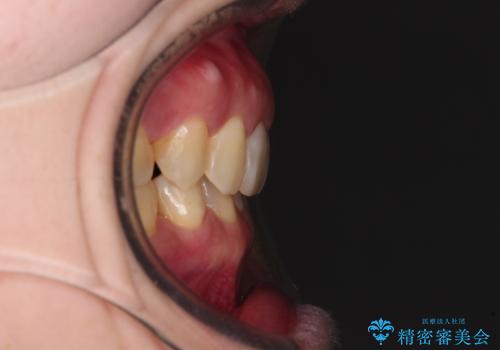

下顎2前歯の欠損 インビザラインによる抜歯矯正

- 下顎前歯欠損による歯列不正を気にして来院された患者様です。

下顎の歯列が小さく、下顎前歯が隠れてしまう過蓋咬合(ディープバイト)であったため、